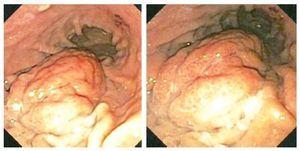

Mujer de 41 años, que se presentó a consulta con un gastroenterólogo por dolor abdominal alto, de tres meses de evolución, inespecífico, sin factores que lo atenuaran o exacerbaran. Fue evaluada mediante endoscopia con la que se evidenció tumoración gástrica submucosa (Figura 1). La biopsia superficial reveló gastritis moderada. La paciente fue referida a ultrasonido endoscópico que confirmó masa submucosa con zonas quísticas consistentes con necrosis de 4 cm por 4 cm (Figura 2). Se estableció el diagnóstico endoscópico de probable tumor del estroma gastrointestinal y la paciente se envió a cirugía. Se le realizó una resección distal gástrica en cuña y el análisis histopatológico reveló duplicación gástrica congénita de 4 cm. La paciente se recuperó sin complicaciones.

¿ Figura 1. Vista endoscópica de la masa.